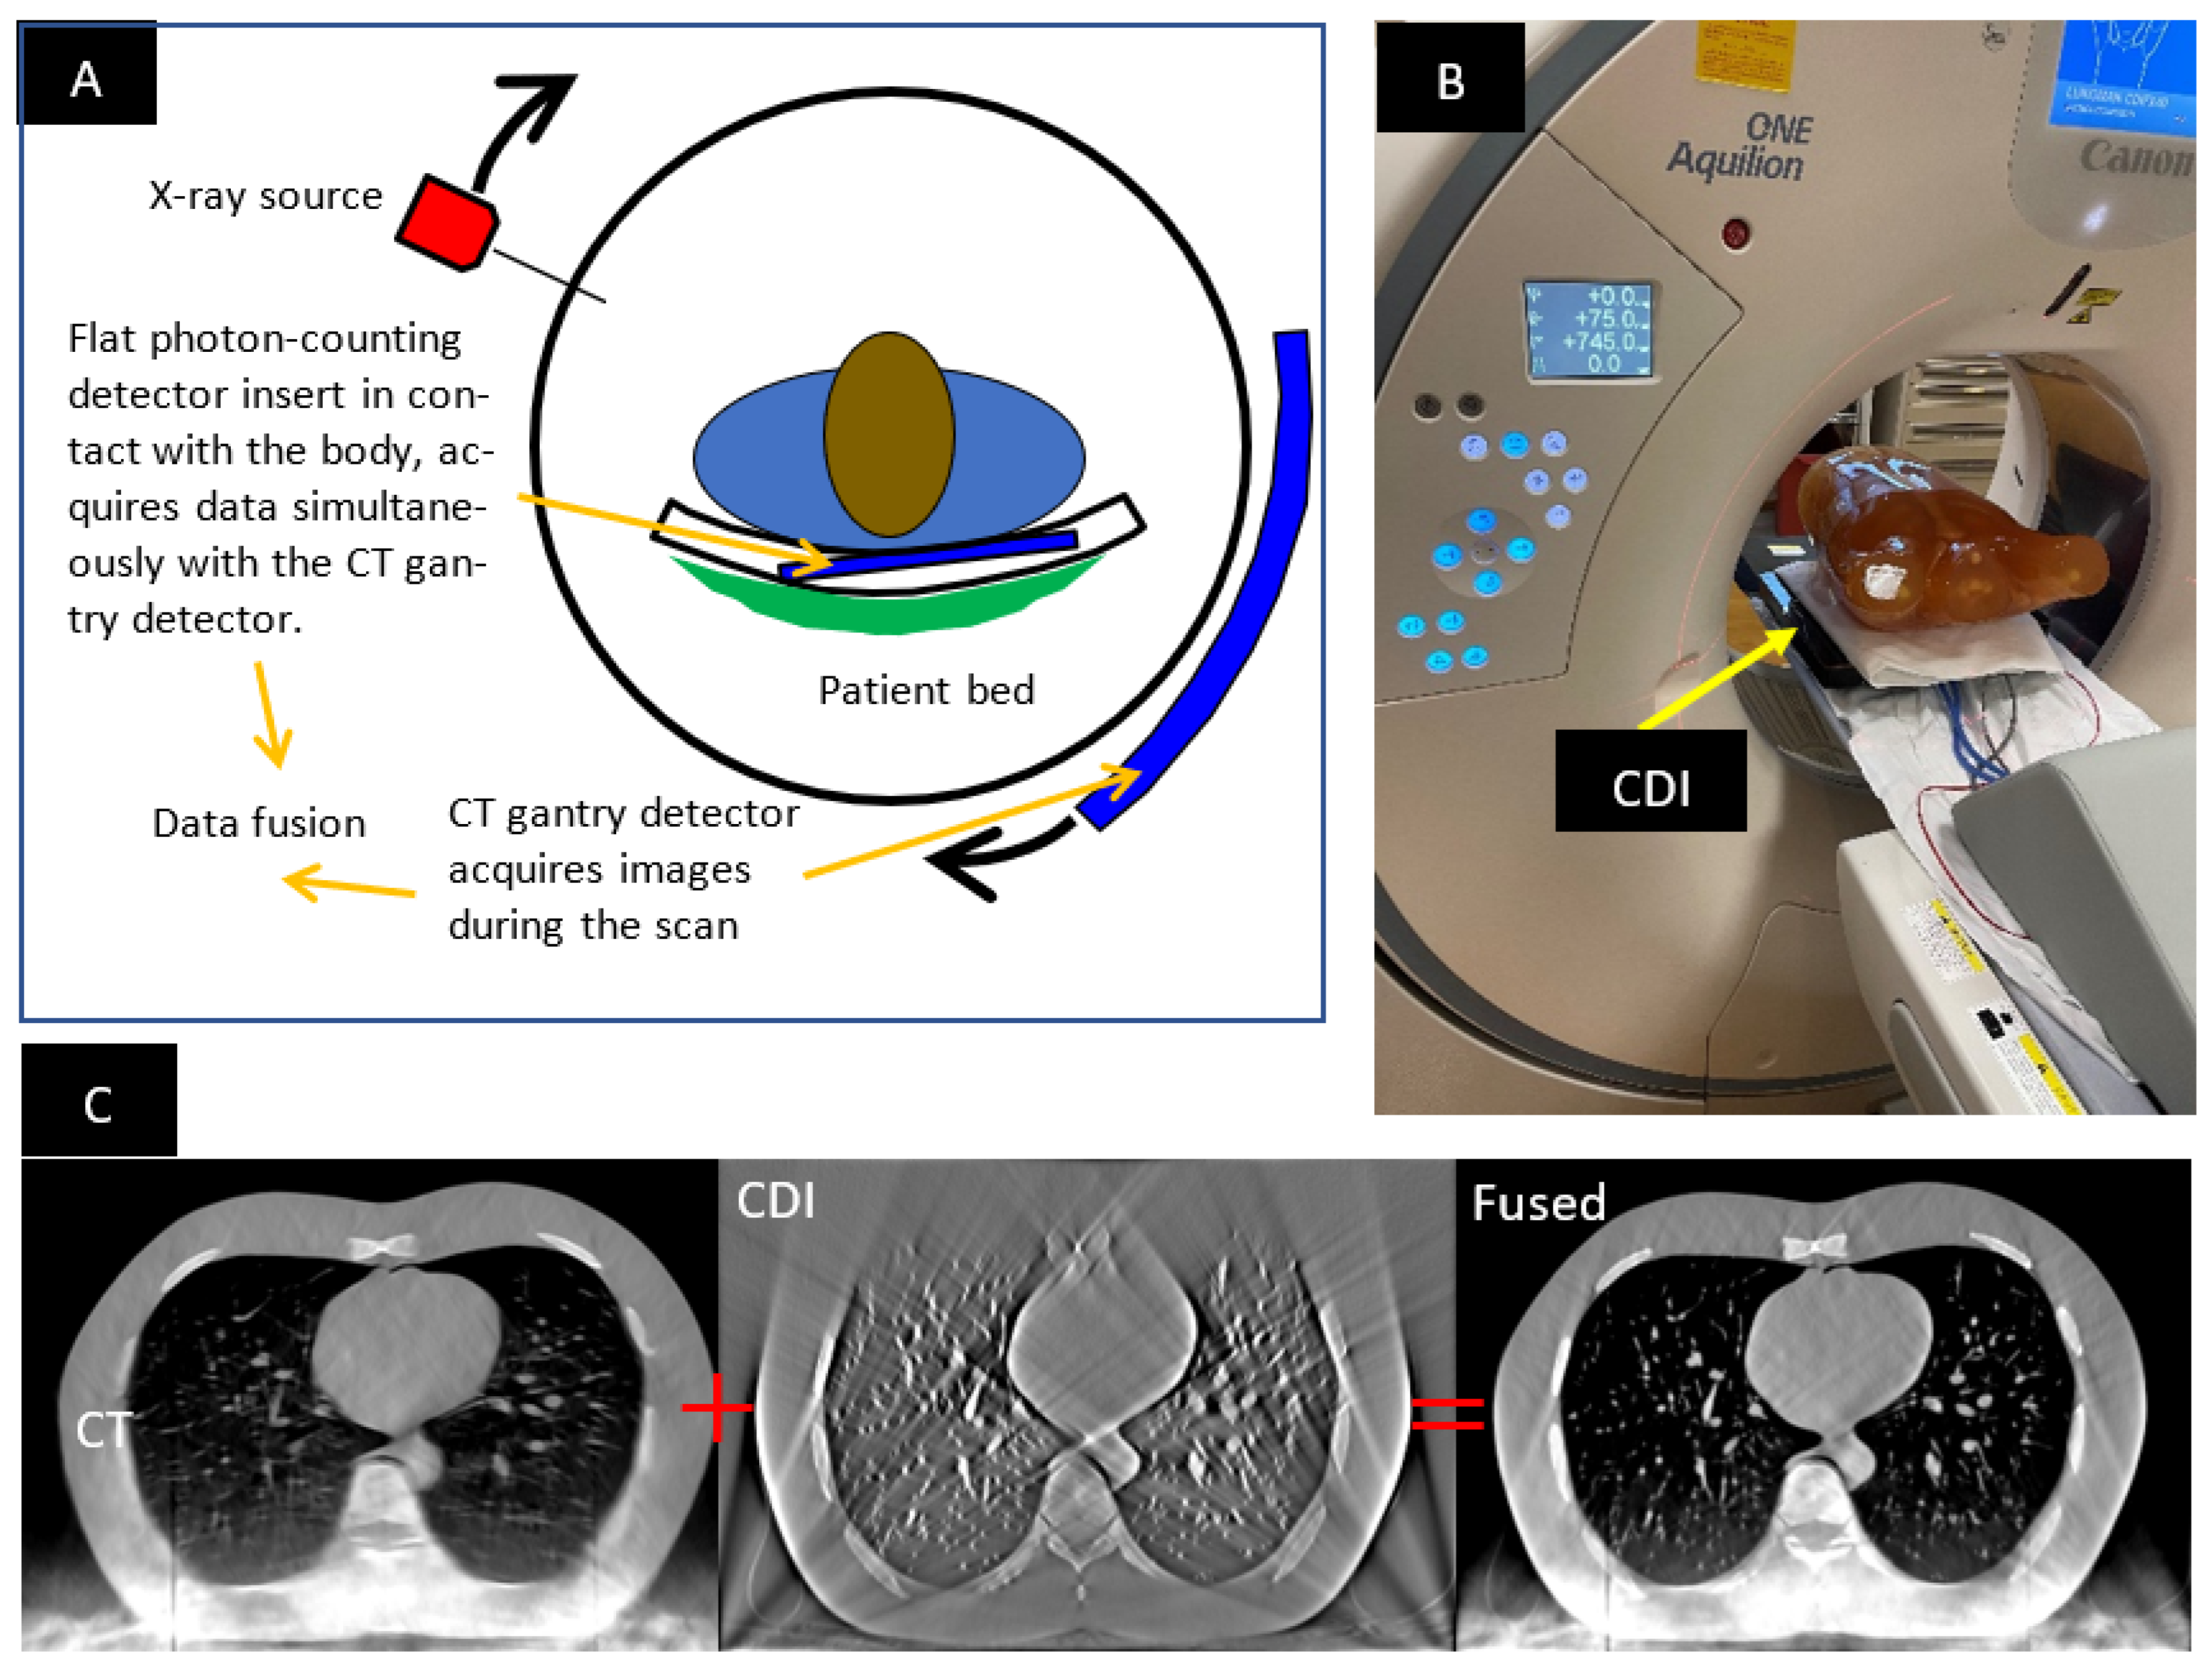

Tomography | Free Full-Text | Online Geometric Calibration Of A Hybrid

www.mdpi.com

www.mdpi.com

‘Thinking Outside The Bottle’ – Hybrid Dental CT Scanner Performs 3D

xray3d.com

xray3d.com

‘Thinking Outside The Bottle’ – Hybrid Dental CT Scanner Performs 3D

xray3d.com

xray3d.com